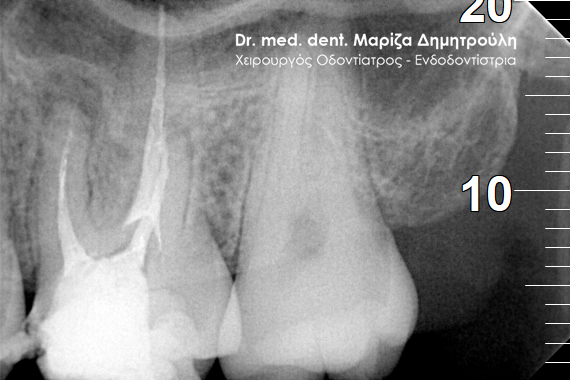

Root canal treatment

BEFORE